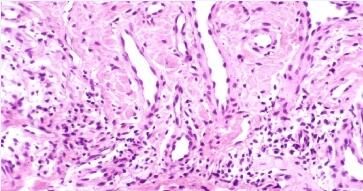

丘疹性荨麻疹症状特点:

突然出现的风团样丘疹,呈圆形或纺锤形,黄豆至蚕豆大小,伴有轻度水肿,淡红或鲜艳。

炎症明显时中心有水疱,甚至形成张力性大疱,自觉剧痒。皮损多发于四肢、躯干,呈散在或群集分布,有时可见3—4个丘疹呈线状排列。

皮损可分批出现,新旧交替或重叠。本病有自限性,每批皮损约经3—7天,皮损消退后遗留色素沉着。